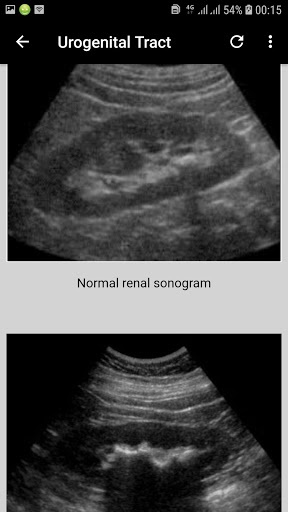

Interpretation of Skull, paranasal sinuses, orbit, chest, abdomen, urogenital tract (pelvis), and musculoskeletal x-rays.